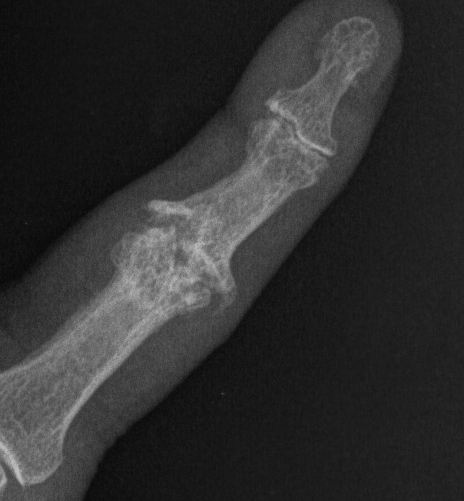

Xray

Joint space narrowing

Subchondral sclerosis

Osteophyte formation